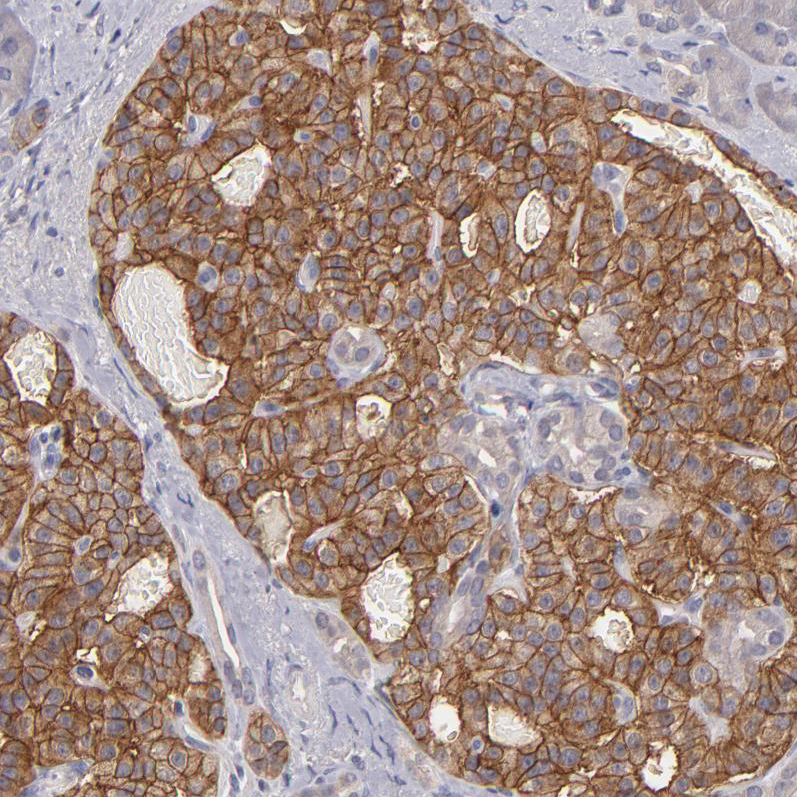

Immunohistochemistry analysis in human cerebral cortex and liver tissues using HPA003011 antibody. Corresponding GNAZ RNA-seq data are presented for the same tissues.